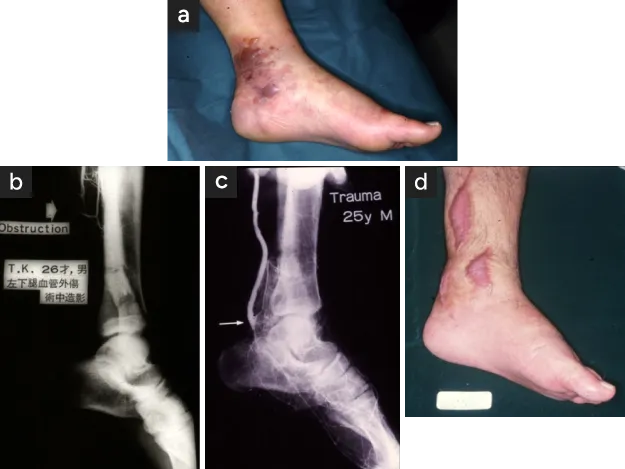

簡単な治療なので患者さんの体への負担は小さいのですが、血管を無理に押し広げるため血管が広がると同時に血管の壁が高度に傷害されます。血管の壁、特に内膜(壁の内側)に裂け目ができるかはがれてきます。それにより足部は血流が少ないので急性血栓症により重症血行障害を発生する危険性があります。〈図1a,b,c,d〉にカテーテル治療後の血管傷害により救済に難渋した例や救済不可能となった例を提示します。

早期に異常を発生せず血行障害が改善に向かったとしてもそれは一時的で長期的には異常を発生します。傷害を受けた血管壁の細胞は長期的に死滅します。“徹底的に血管を広げました”と言う医師がいますが、それは“徹底的に血管を傷害しました”ということですので、その後に起こってくる生体反応が重大な問題を引き起こすことを知るべきです。

傷害された血管は修復しようと反応をはじめます。内面に平滑な膜が形成されますが、問題はこの膜が一定で治まらずに厚さを増し続け(内膜肥厚といい、血管内側の壁が厚くなってくる生体反応)、内腔が再び狭くなってきます。これが再狭窄といわれる合併症で放置されると血管は再狭窄・再閉塞を発生すると同時に壊疽は悪化します。

この反応は1~数か月の間に発生し、全く治療前の状態に戻ってしまい、その過程で壊疽は一層拡大します〈図2a,b〉。